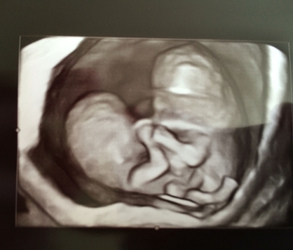

caption@callieandcarterbeatodds / CATERS NEWS (PICTURED A scan of the conjoined twins) A mum says her conjoined twins are defying the odds after they have learnt to walk and are now living their best life. Chelsea Torres, 30, was told that her conjoined twin girls, Callie and Carter, now six, would not survive longer than 24 hours after they were born. Now, six years on, Callie and Carter, who are separate from their bellies up, have defied the odds and have just learnt to walk and are about to start first grade at school. Chelsea, from Idaho, US, added: "It has taken them almost seven years to be able to learn to walk, but we have managed to get there and they're doing so well now. SEE CATERS COPY